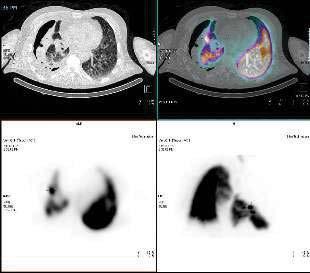

Background: A 56 year old male with productive cough, headache and lethargy presented to the Emergency Department febrile and with dyspnoea.

A CT scan showed collapse of the right lung due to a large tension pneumothorax. A chest x-ray confirmed mediastinal shift to the left. An intercostal chest catheter was inserted, initially resulting in improvement of breathing, Chest x-ray confirmed placement of the chest drain and interval reduction in the size of the pneumothorax. Serial chest x-rays over the next few days showed interval enlargement of the pneumothorax. The chest-drainage system showed persistent bubbling in the water seal chamber, prompting the treating team to consider the possibility of a persistent air leak.

Method: A ventilation Nuclear Medicine lung scan was performed using 500MBq 99mTc-Pertechnetate loaded into the Technegas generator. The referring Thoracics Physician accompanied the patient to clamp off the chest drain, assess the patient throughout and to open the drain once imaging was complete.

Inhalation of 99mTc-Technegas continued until 5K counts were seen from the posterior image on the pscope.

A Siemens Intevo gamma camera was used to acquire anterior and posterior dynamic images, followed by a SPECT/CT scan.

Results: Foci of increased tracer uptake was seen in the midzone of the collapsed right lung, concluding that the air leak was at the lateral segment of the right middle lobe.

Discussion: Following the scan, the patient underwent insertion of an Endobronchial valve into the right middle lobe. This procedure requires accurate localization of the site of the persistent air leak. Options to localise persistent air leaks are limited and invasive. Other medical imaging modalities offer minimal diagnostic information.

Conclusion: The Nuclear Medicine ventilation scan was immensely valuable in localizing the site of a persistent air leak. The findings of our study enabled a life-saving endo-bronchial valve to be accurately inserted. A chest x-ray taken 10 weeks later showed inflation of the formerly collapsed lung, indicating resolution of the pneumothorax.

Figure 1: SPECT/CT Transverse slices, showing the suspected air leak.